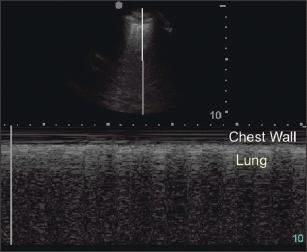

Because air accumulates in a nondependent manner, examination of the anterior chest of the supine patient is optimal for the exclusion of pneumothorax. Using this technique, the absence of lung sliding has a sensitivity that is comparable to the sensitivity of CT scanning. Documentation of lung sliding for the medical record can be accomplished by switching the ultrasound to motion mode (M-mode) and observing the "seashore sign" (Figure 4).

Figure 4 –

This split-screen display of pleural ultrasonography includes the normal display (top) and M-mode display with "seashore sign" (bottom).